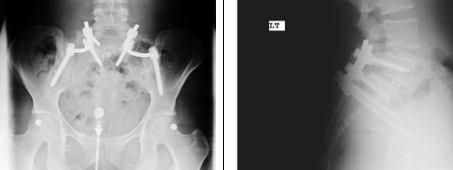

I received this encouraging word today from Chrissie, a 34 yo woman who had a very painful L5S1 spondylolisthesis with a pars fracture which really interfered with her quality of life.

Dr. Hey met with me and reviewed all my MRIs, x-rays and options. Then we talked about the possibilities that he could open up for me by going through surgery. I was once a very active person—I had played some college basketball and since then had grown to love working out, running and other sports. But my back pain had all but brought these loves to a halt. I had the mentality of “I can’t.” I couldn’t run anymore, I couldn’t jog, even. Lifting was difficult. Even picking up one of my four children was taking its toll.